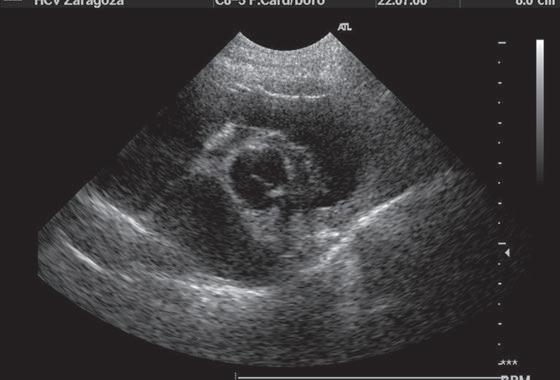

Juan José Esteban Jiménez / Experto Universitario en TC, Experto Universitario en Urgencias de Pequeños Animales y CertSAS / Facultad de Veterinaria de Zaragoza Figura 1. Visión eje corto Ai/Ao. Figura 2. Modo M mitral.

evidencia actual que va quedando claras. En 2020, el estudio DELay dirigido por Borgarelli obtuvo unos resultados muy similares a los encontrados en mi tesis en los que solamente el iECA con espironolactona mostraba eficacia clínica (en estadio B2). Se están poniendo en entredicho valores concretos del ratio Ai/Ao (figura 1), de las medidas ventriculares normalizadas, incluso si es específico de cada raza. Fármacos como el pimobendán parecen tener diferentes semividas en los pacientes, aunque comienza a notificarse que puede ser útil en fases preclínicos, por lo que queda mucho terrero por estudiar.